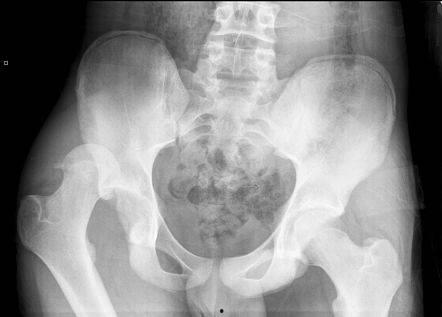

首先,我们要明确一点,骨盆大小确实在一定程度上影响着身材比例。一般来说,骨盆宽的女性,身材曲线会更加明显,而骨盆窄的女性,身材则相对较为苗条。但这并不意味着骨盆大小就能完全决定一个人的身材。

据《美国流行病学杂志》的研究,骨盆大小与遗传、生活方式、饮食习惯等因素都有关系。所以,即使骨盆大小不同,只要保持健康的生活方式,也能拥有令人羡慕的身材。

1. 腰臀比:骨盆大小与腰臀比有着密切的关系。一般来说,骨盆宽的女性,腰臀比会更大,身材曲线更加明显。